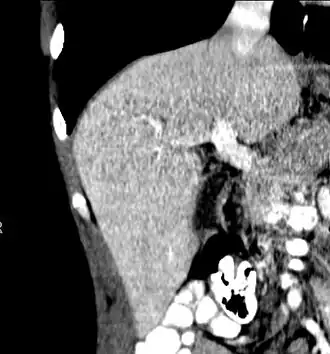

Maximum intensity projection (MIP) CT image as viewed anteriorly showing the anomalous hepatic veins coursing on the anterior surface of the liver -

Lateral MIP view in the same patient as previous image -